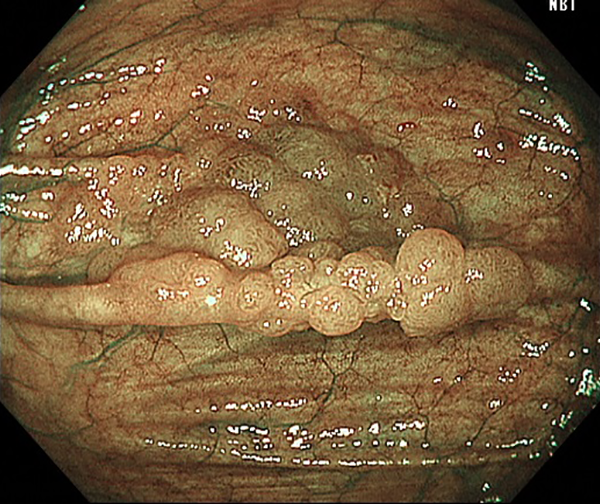

④盲腸癌(側方発育型腫瘍(LST))

1. 大腸癌検診の便潜血陽性で内視鏡検査を施行、盲腸のヒダ上に小さな不整隆起を認めます。

2. NBI画像処理で側方発育型腫瘍(顆粒型)径20mmを認めます。内視鏡的粘膜切除術で治癒、粘膜内癌と診断されました。